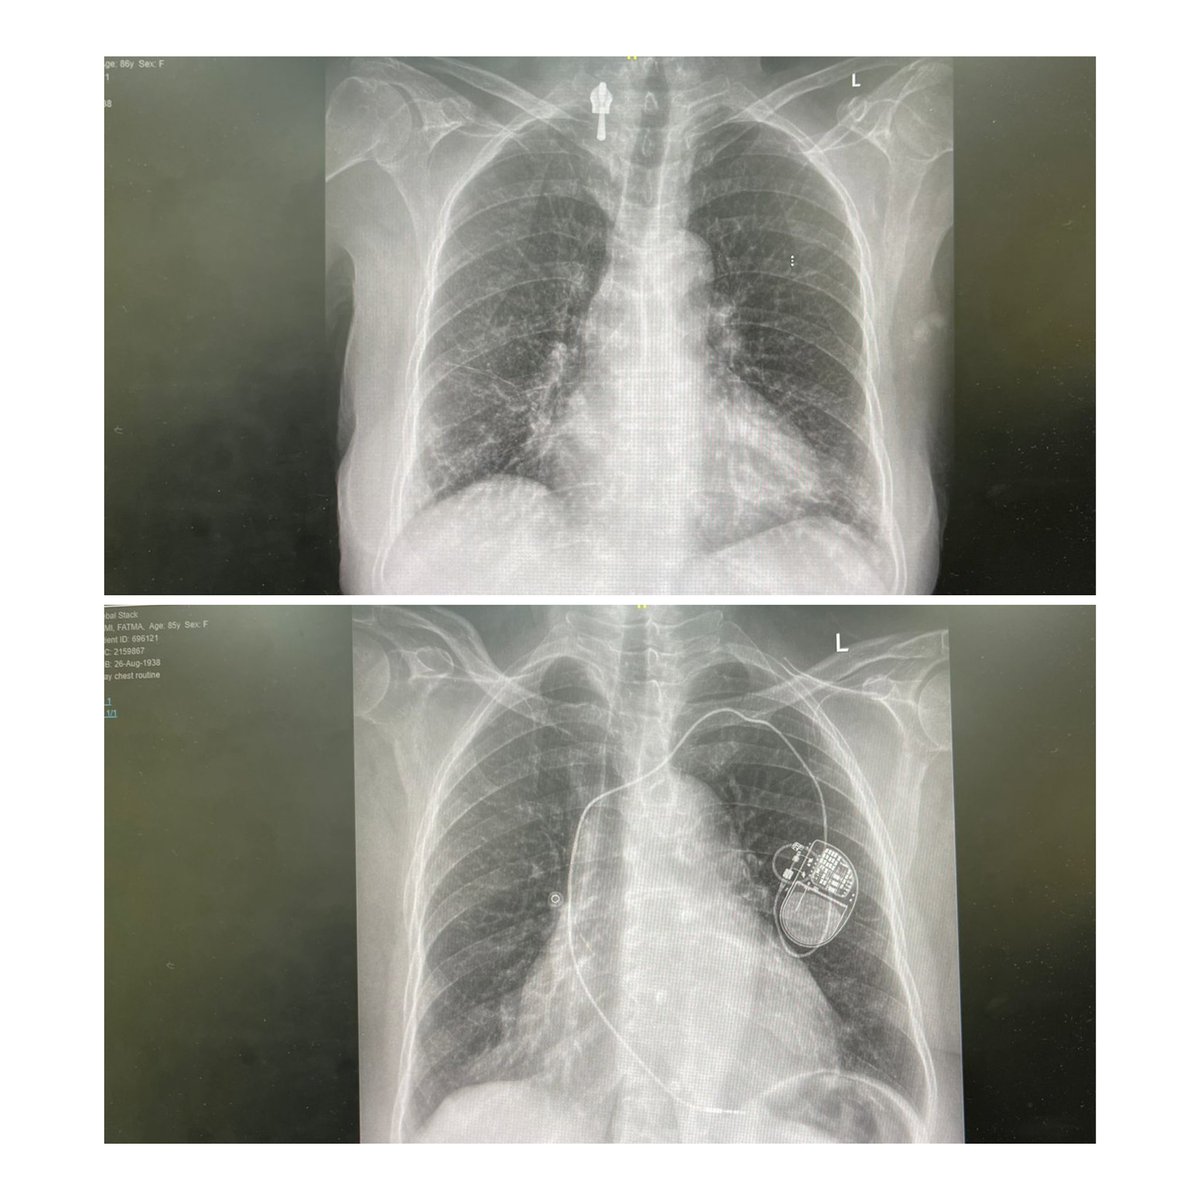

⚠️ Shocking X-ray Mistake! Pacemaker Disappeared? 🫀🔍 By Mohammad I.Al-Assiri A patient presented with chest pain, and we were shocked to find no pacemaker on the X-ray, despite one being implanted two months earlier. Upon review, it was discovered that a radiology technician had